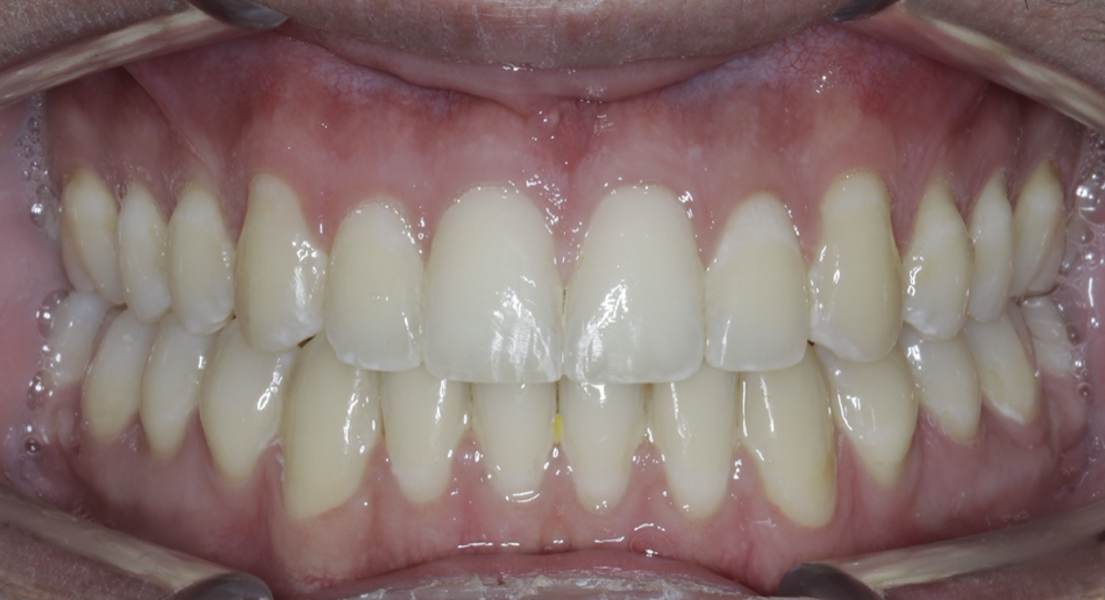

New Age orthodontics and orthopaedics with temporary anchorage devices